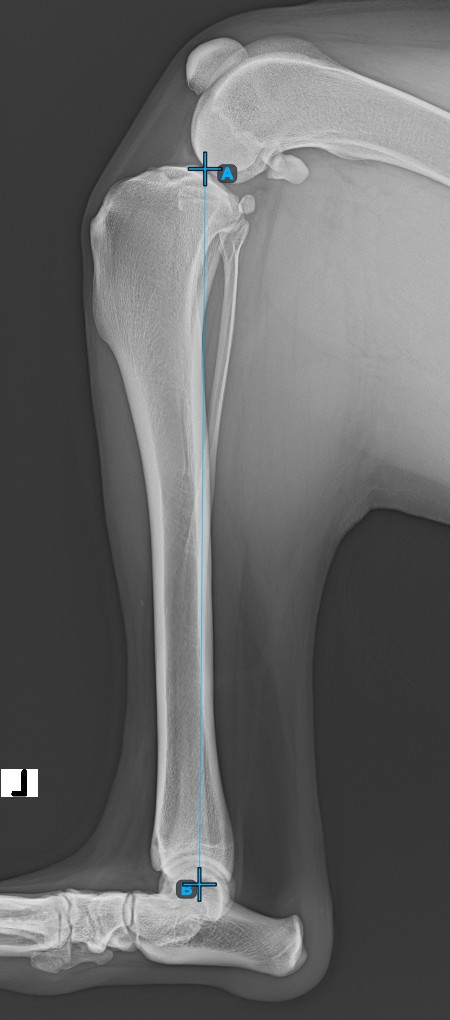

Folytassa a mérést a Cochlea középpontjának megjelölésével, amely a tibia csont végén található. Az Eminentia Intercondylaris és a Cochlea középpontja közötti vonal a tibia hosszanti tengelyét reprezentálja.

A lenti kép a Cochlea középpontjának szokásos elhelyezkedését ábrázolja.